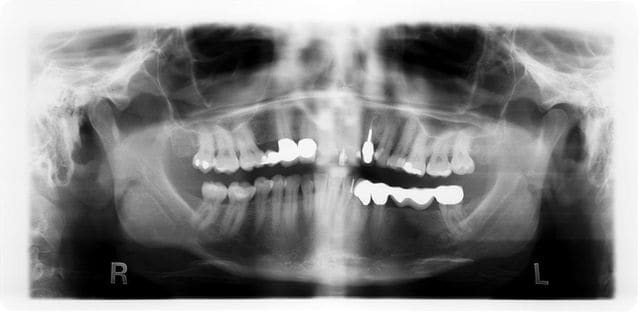

j'aurais bien aimé connaitre votre avis au sujet de cette Radio panoramique qui révèle une image radioclaire/ au centre opaque, au niveau de la Racine mesiale de la 37, patient n'a pas douleur.

16/06/2012 à 21h00

Apex résiduel

au fond du canal

19/06/2012 à 11h24

A laisser tranquille